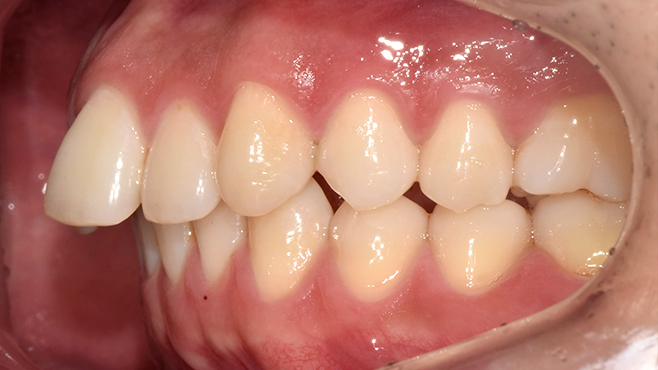

실제 치료 사례

수많은 환자들이 고민 끝에 선택한 치료,

그리고 그 후의 놀라운 변화

- ※ 위 임상사진은 365서울원탑치과에서 진료를 시작하고 마친 동일한 환자의 사진입니다.

- ※ 위 임상사진은 동일한 장소에서 동일한 조건으로 촬영되었으며, 사진에 대한 별도의 조작이 처리되지 않았습니다.

- ※ 수술 및 치료 과정에서 부작용이 발생할 수 있으므로 의료진과의 충분한 상담과 신중한 판단이 요구됩니다.